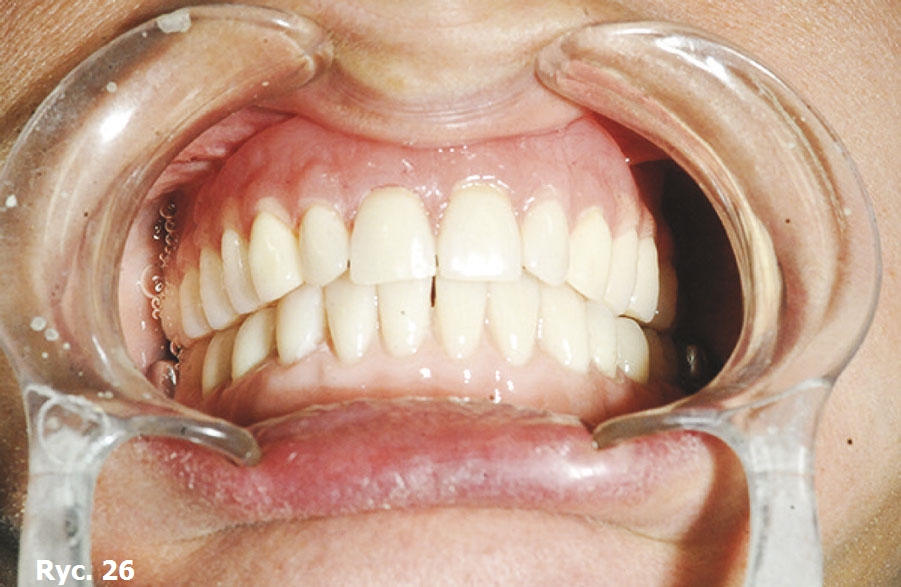

Wyniki badania TK oraz model stereolitograficzny pozwoliły na wykonanie dwóch oddzielnych siatek wszczepu podokostnowego w obrębie łuku górnego (ryc. 9), które zostały później wszczepione (ryc. 10) oraz połączone ze sobą, aby wspólnie przenosić siły żucia (ryc. 11), stanowiąc podparcie dla estetycznego uzupełnienia protetycznego stałego (ryc. 12, 13). Zabieg chirurgiczny przebiegł bez powikłań. Przysłana z Karaibów kartka pocztowa z trzema słowami „drugi miesiąc miodowy” potwierdziła, że cała wykonana przez lekarza praca zakończyła się sukcesem.